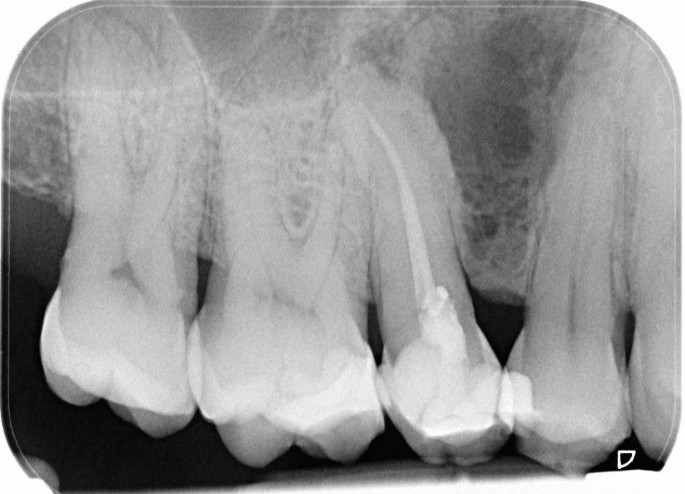

A multilocular radiolucent lesion was found in the interdental bone between the upper first and second premolars. The teeth were vital and after enucleation, the pathologist reported that the cyst had features of a developmental periodontal cyst lined by squamous epithelium with focal thickened areas.